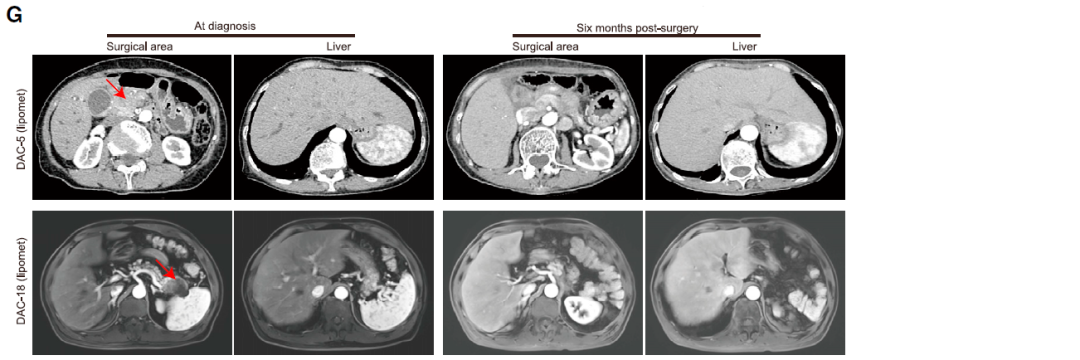

作者进一步分析代谢亚型的预后意义和治疗意义。将代谢亚型与临床结果关联,根据代谢特征基因的表达将Bailey PDAC队列(n = 55例)和TCGA PDAC队列(n = 156例)分为两个亚型。在这两个队列中,glucomet-PDAC患者的总生存率明显低于lipomet-PDAC。然后使用吉西他滨(GEM)、5-氟尿嘧啶(5-FU)、伊立替康(IRI)和奥沙利铂(OXA)(四种通过抑制DNA合成起作用的化疗药物)进一步评估两种亚型的化疗敏感性,结果显示,glucomet-PDAC通常比lipomet-PDAC类器官的耐药性更强。

表明,glucomet-PDAC具有化疗耐药性,且与较差的预后相关!